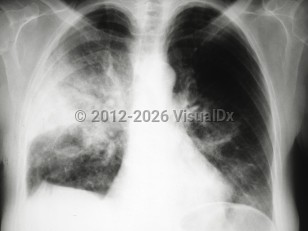

Pneumothorax

Spontaneous pneumothoraxSpontaneous pneumothorax

Tension pneumothorax